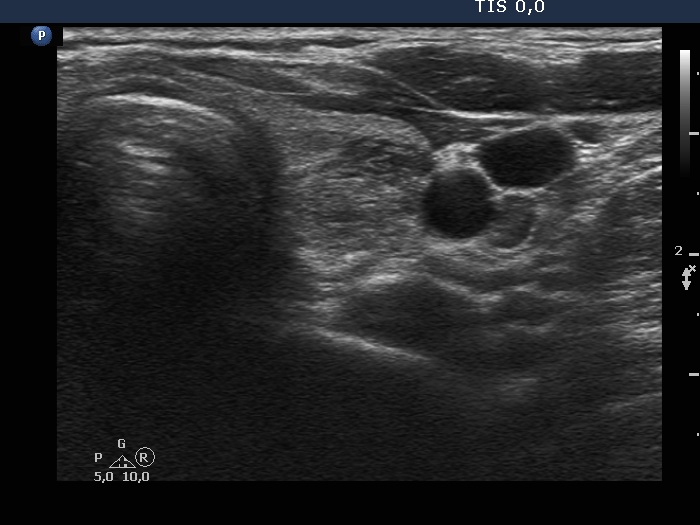

Ultrasonography. The thyroid was echonormal and had multiple moderately hypoechoic and hyperechoic nodules which showed various degrees of cystic degeneration. The largest nodule in the right lobe was dominantly cystic and presented with minimally hypoechoic solid part which included hyperechoic figures. The largest nodule in the left lobe had irregular margins.

2.5 mL cystic fluid was aspirated from the right nodule. Thereafter, the borders became irregular, lobulated. Aspiration cytology of the solid part after the removal of cystic fluid an that of the nodule having irregular borders in the left lobe resulted in bening cystic degeneration.

The right nodule presented with a patchy echonormal area having punctate echogenic foci, a pattern resembling amyloid deposit.